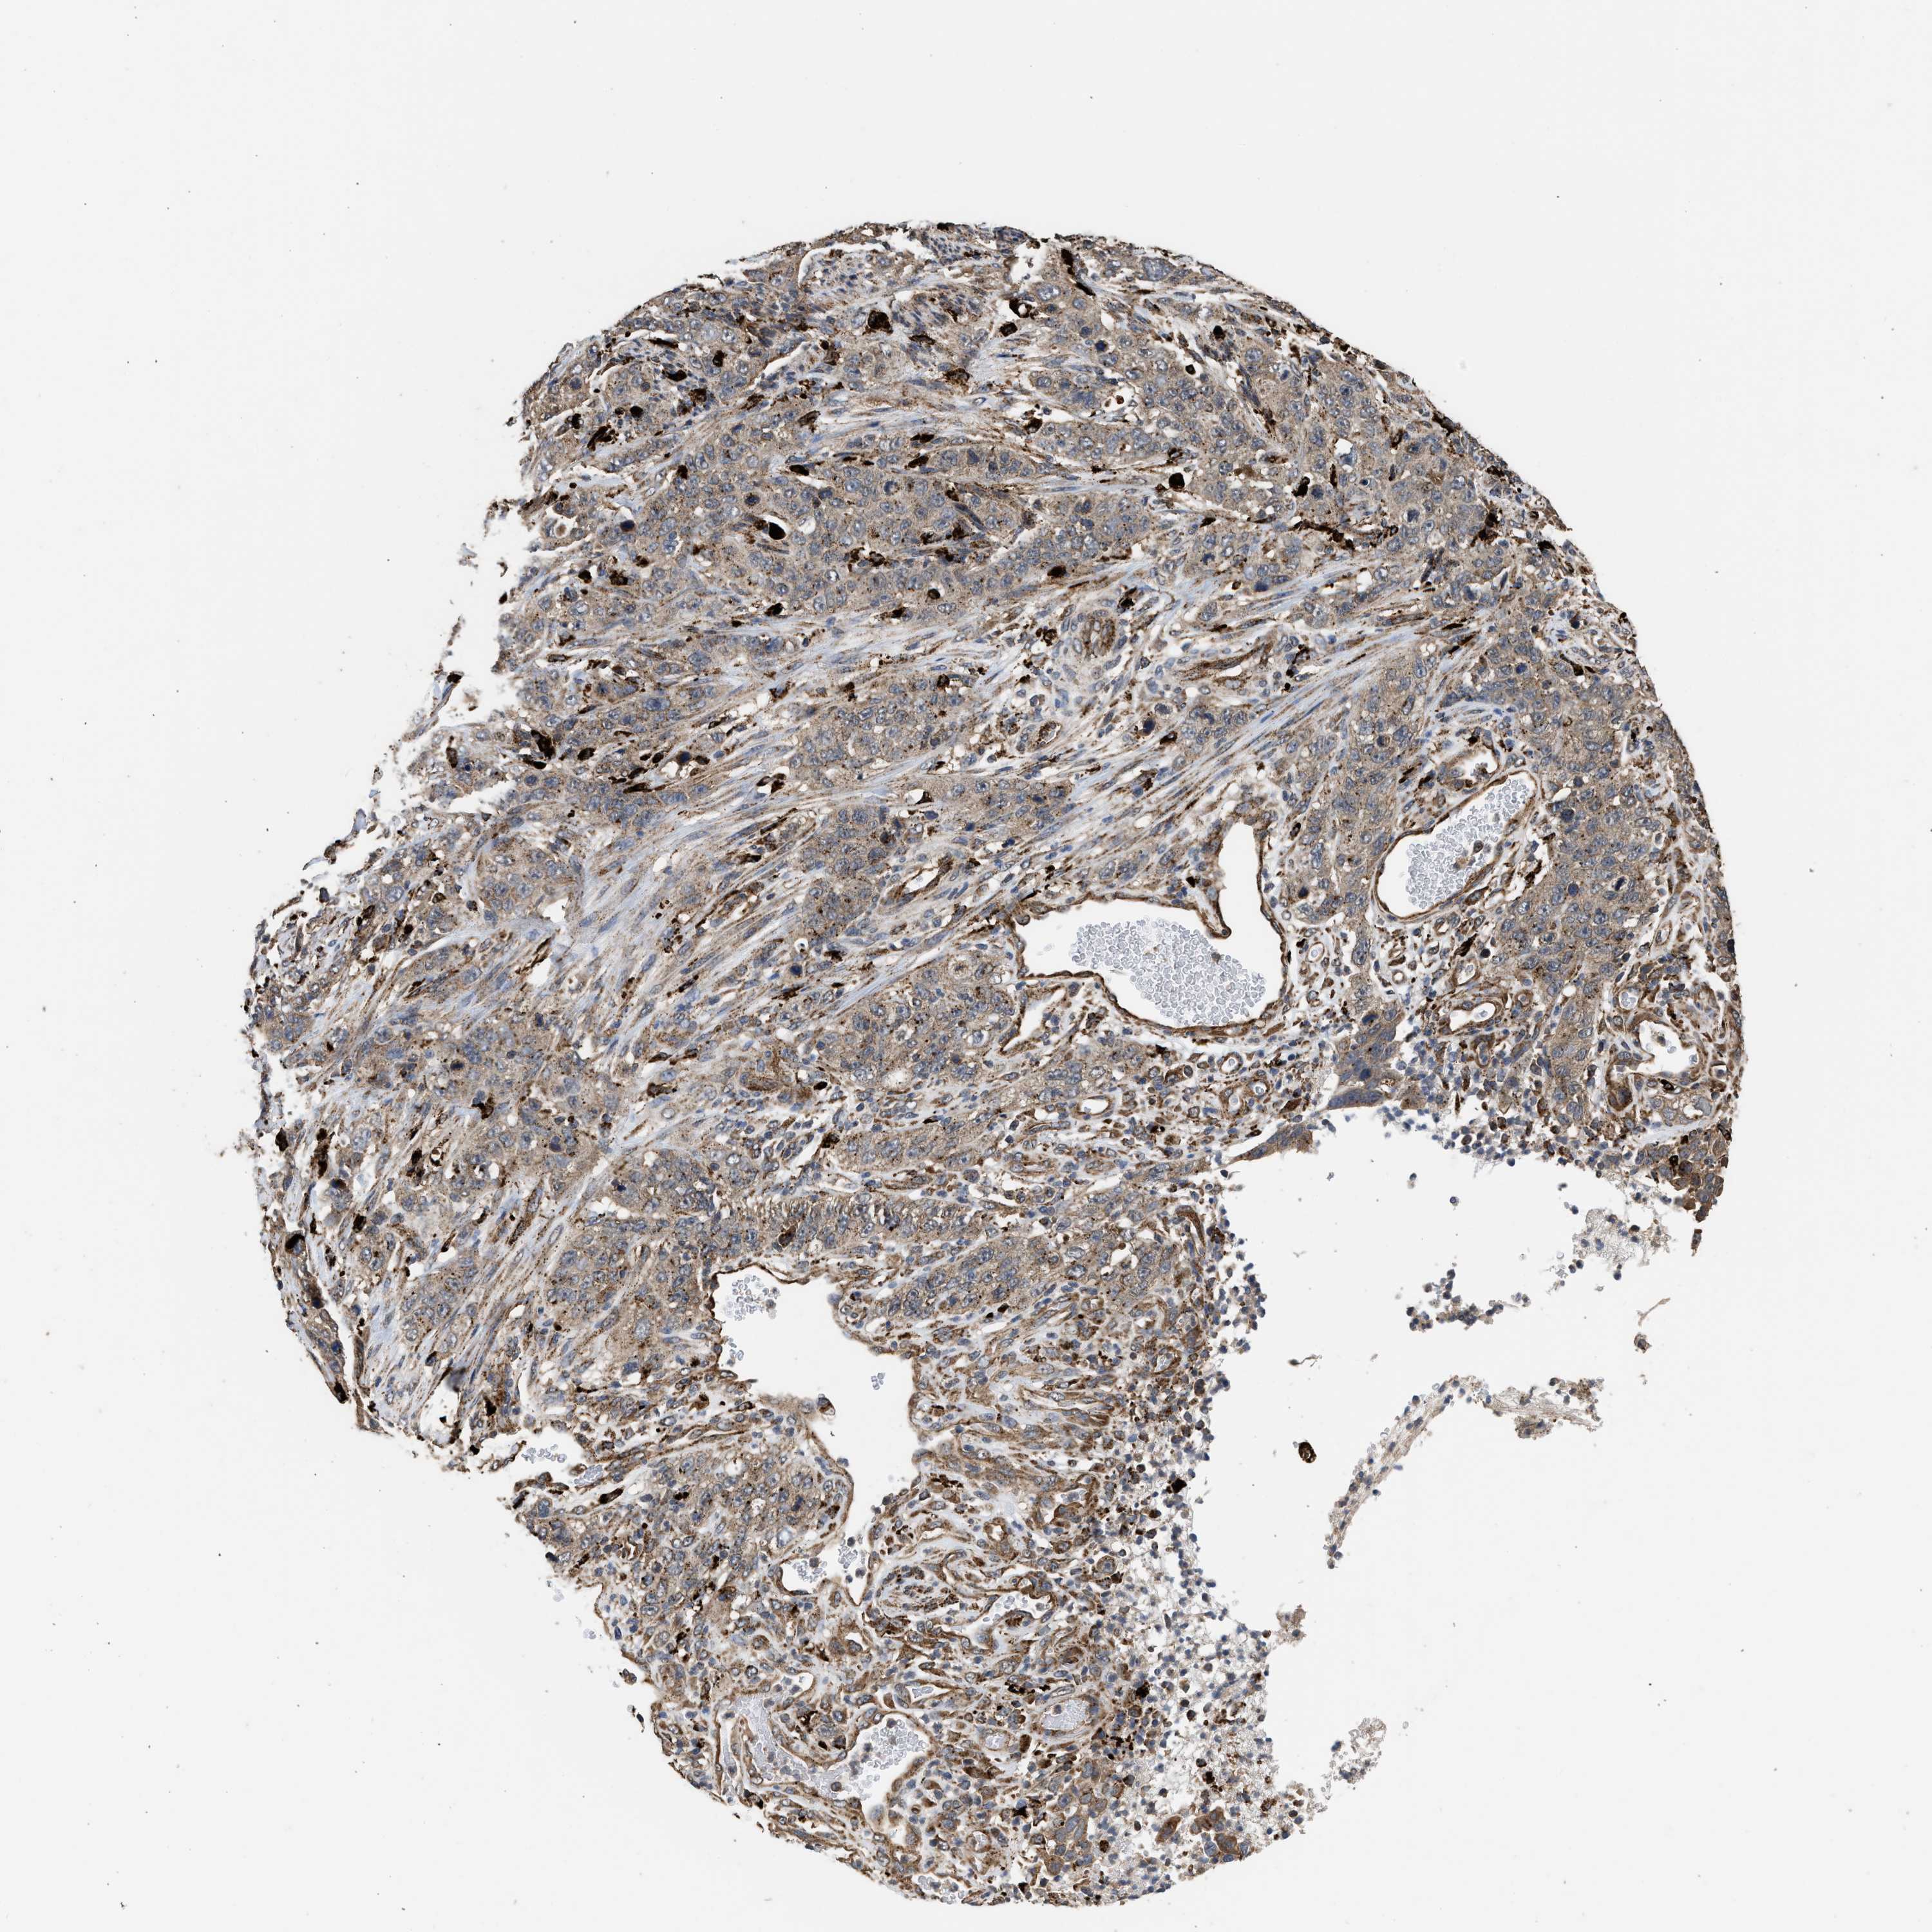

STOMACH CANCER - Protein expressioni

A mouse-over function shows sample information and annotation data. Click on an image to view it in a full screen mode. Samples can be filtered based on level of antibody staining by selecting one or several of the following categories: high, medium, low and not detected. The assay and annotation is described here.

Note that samples used for immunohistochemistry by the Human Protein Atlas do not correspond to samples in the TCGA dataset.

Antibody stainingi

Antibody staining in the annotated cell types in the current human tissue is reported as not detected, low, medium, or high, based on conventional immunohistochemistry profiling in selected tissues. This score is based on the combination of the staining intensity and fraction of stained cells.

Each image is clickable and will lead to virtual microscopy that enables deeper exploration of all samples and also displays staining intensity scores, fraction scores and subcellular localization as well as patient and tissue information for each sample.

Antibody CAB017112

Staining

High

Medium

Low

Not detected

Intensity

Strong

Moderate

Weak

Negative

Quantity

>75%

75%-25%

<25%

None

Location

Nuclear

Cytoplasmic/membranous

Cytoplasmic/membranous,nuclear

Adenocarcinoma, NOS

Adenocarcinoma, High grade